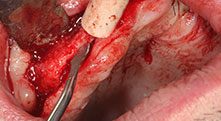

Bratu: Utilizamos los insertos de forma rutinaria para la extracción de injertos óseos y la ranuración de las crestas alveolares. También utilizamos las Piezomed B6/B7 para practicar osteotomías en dientes retenidos y no retiramos implantes que pueden conservarse. Todas estas son indicaciones que requieren cortes profundos y limpios.

Bratu: Preferimos realizar las osteotomías en la línea oblicua externa de la cara posterior del maxilar inferior, y no en la región situada entre los orificios. Tras realizar una incisión en los tejidos blandos, utilizamos las nuevas sierras para definir el contorno de la osteotomía. De este modo, conseguimos una preparación completa en prácticamente el 80 por ciento de los casos. Por otro lado, en algunas ocasiones también utilizamos otros insertos piezoquirúrgicos, así como un cincel para mover el injerto. Para nosotros, esta es una técnica de intervención muy eficaz.

Bratu: Nos gusta utilizar la técnica de sándwich para realizar aumentos en la cara lateral del maxilar inferior. En este procedimiento, se utiliza la sierra piezoquirúrgica para preparar una tapa ósea, mientras que el fragmento crestal se fija con microtornillos. Entre medias, colocamos una combinación de hueso autólogo y material óseo adicional xenógeno. Y con ello obtenemos un rendimiento muy fiable. Asimismo, en los ranurados de la cresta alveolar del maxilar inferior, nunca se puede prescindir de cortes verticales suficientemente dimensionados, pues, de lo contrario, los huesos pueden fracturarse fácilmente.